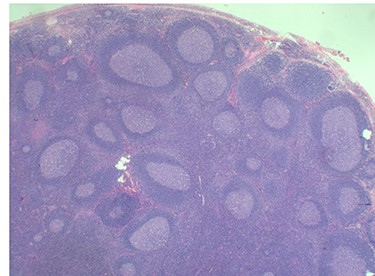

Because of the recent increase in the size of the swelling, the patient presented to our clinic and agreed to undergo excision of the swelling. A well-circumscribed swelling measuring 2.5 cm × 1.5 cm which was soft to firm in consistency was completely excised (Fig. 1). Histopathological examination showed sections of lymph node with florid follicular and germinal center hyperplasia (Fig. 2), and paracortical expansion by plasma cells, small lymphocytes and mast cells (Fig. 3). Marked eosinophilic infiltration with focal micro-abscess formation was present (Fig. 4). The features were consistent with Kimura’s disease. There was no evidence of malignancy. At 6 months follow-up, the patient had no evidence of recurrence.

Histopathology of the lymph node showing an eosinophilic micro-abscess. Haematoxylin and Eosin stain. Magnification ×20.